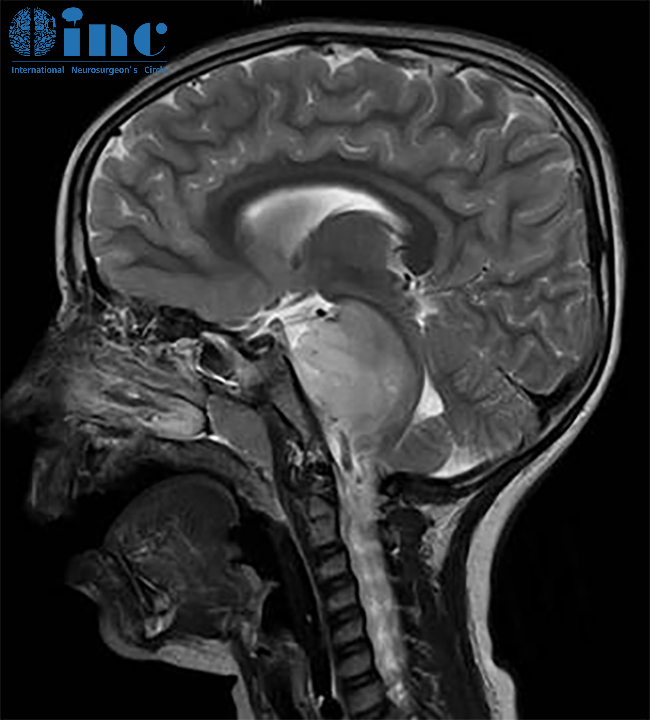

对于胶质瘤治疗,INC巴特朗菲教授提出以下观点:"胶质瘤越早手术效果越好,等待会导致肿瘤进一步增大。本质上,尽早采取行动至关重要,因为肿瘤较小时实现全切的可能性更大,手术风险相对较低,患者预后通常优于肿瘤长大后的情况。因此早期手术是非常必要的。"在示范手术中,巴教授曾建议一名21岁脑干中脑顶盖胶质瘤患者尽早手术。肿瘤直径从8mm增长至18mm,两个月内竟快速增大6mm!肿瘤的迅速增长使全家陷入焦虑,必须尽快找到能安全实施手术的主刀医生。巴教授指出:"这个中脑肿瘤具有明确的手术切除指征,特别是在近期肿瘤尺寸持续增大的情况下。延长等待时间只会给肿瘤更多生长机会,对脑干造成危险,从而加重患者的临床症状。"